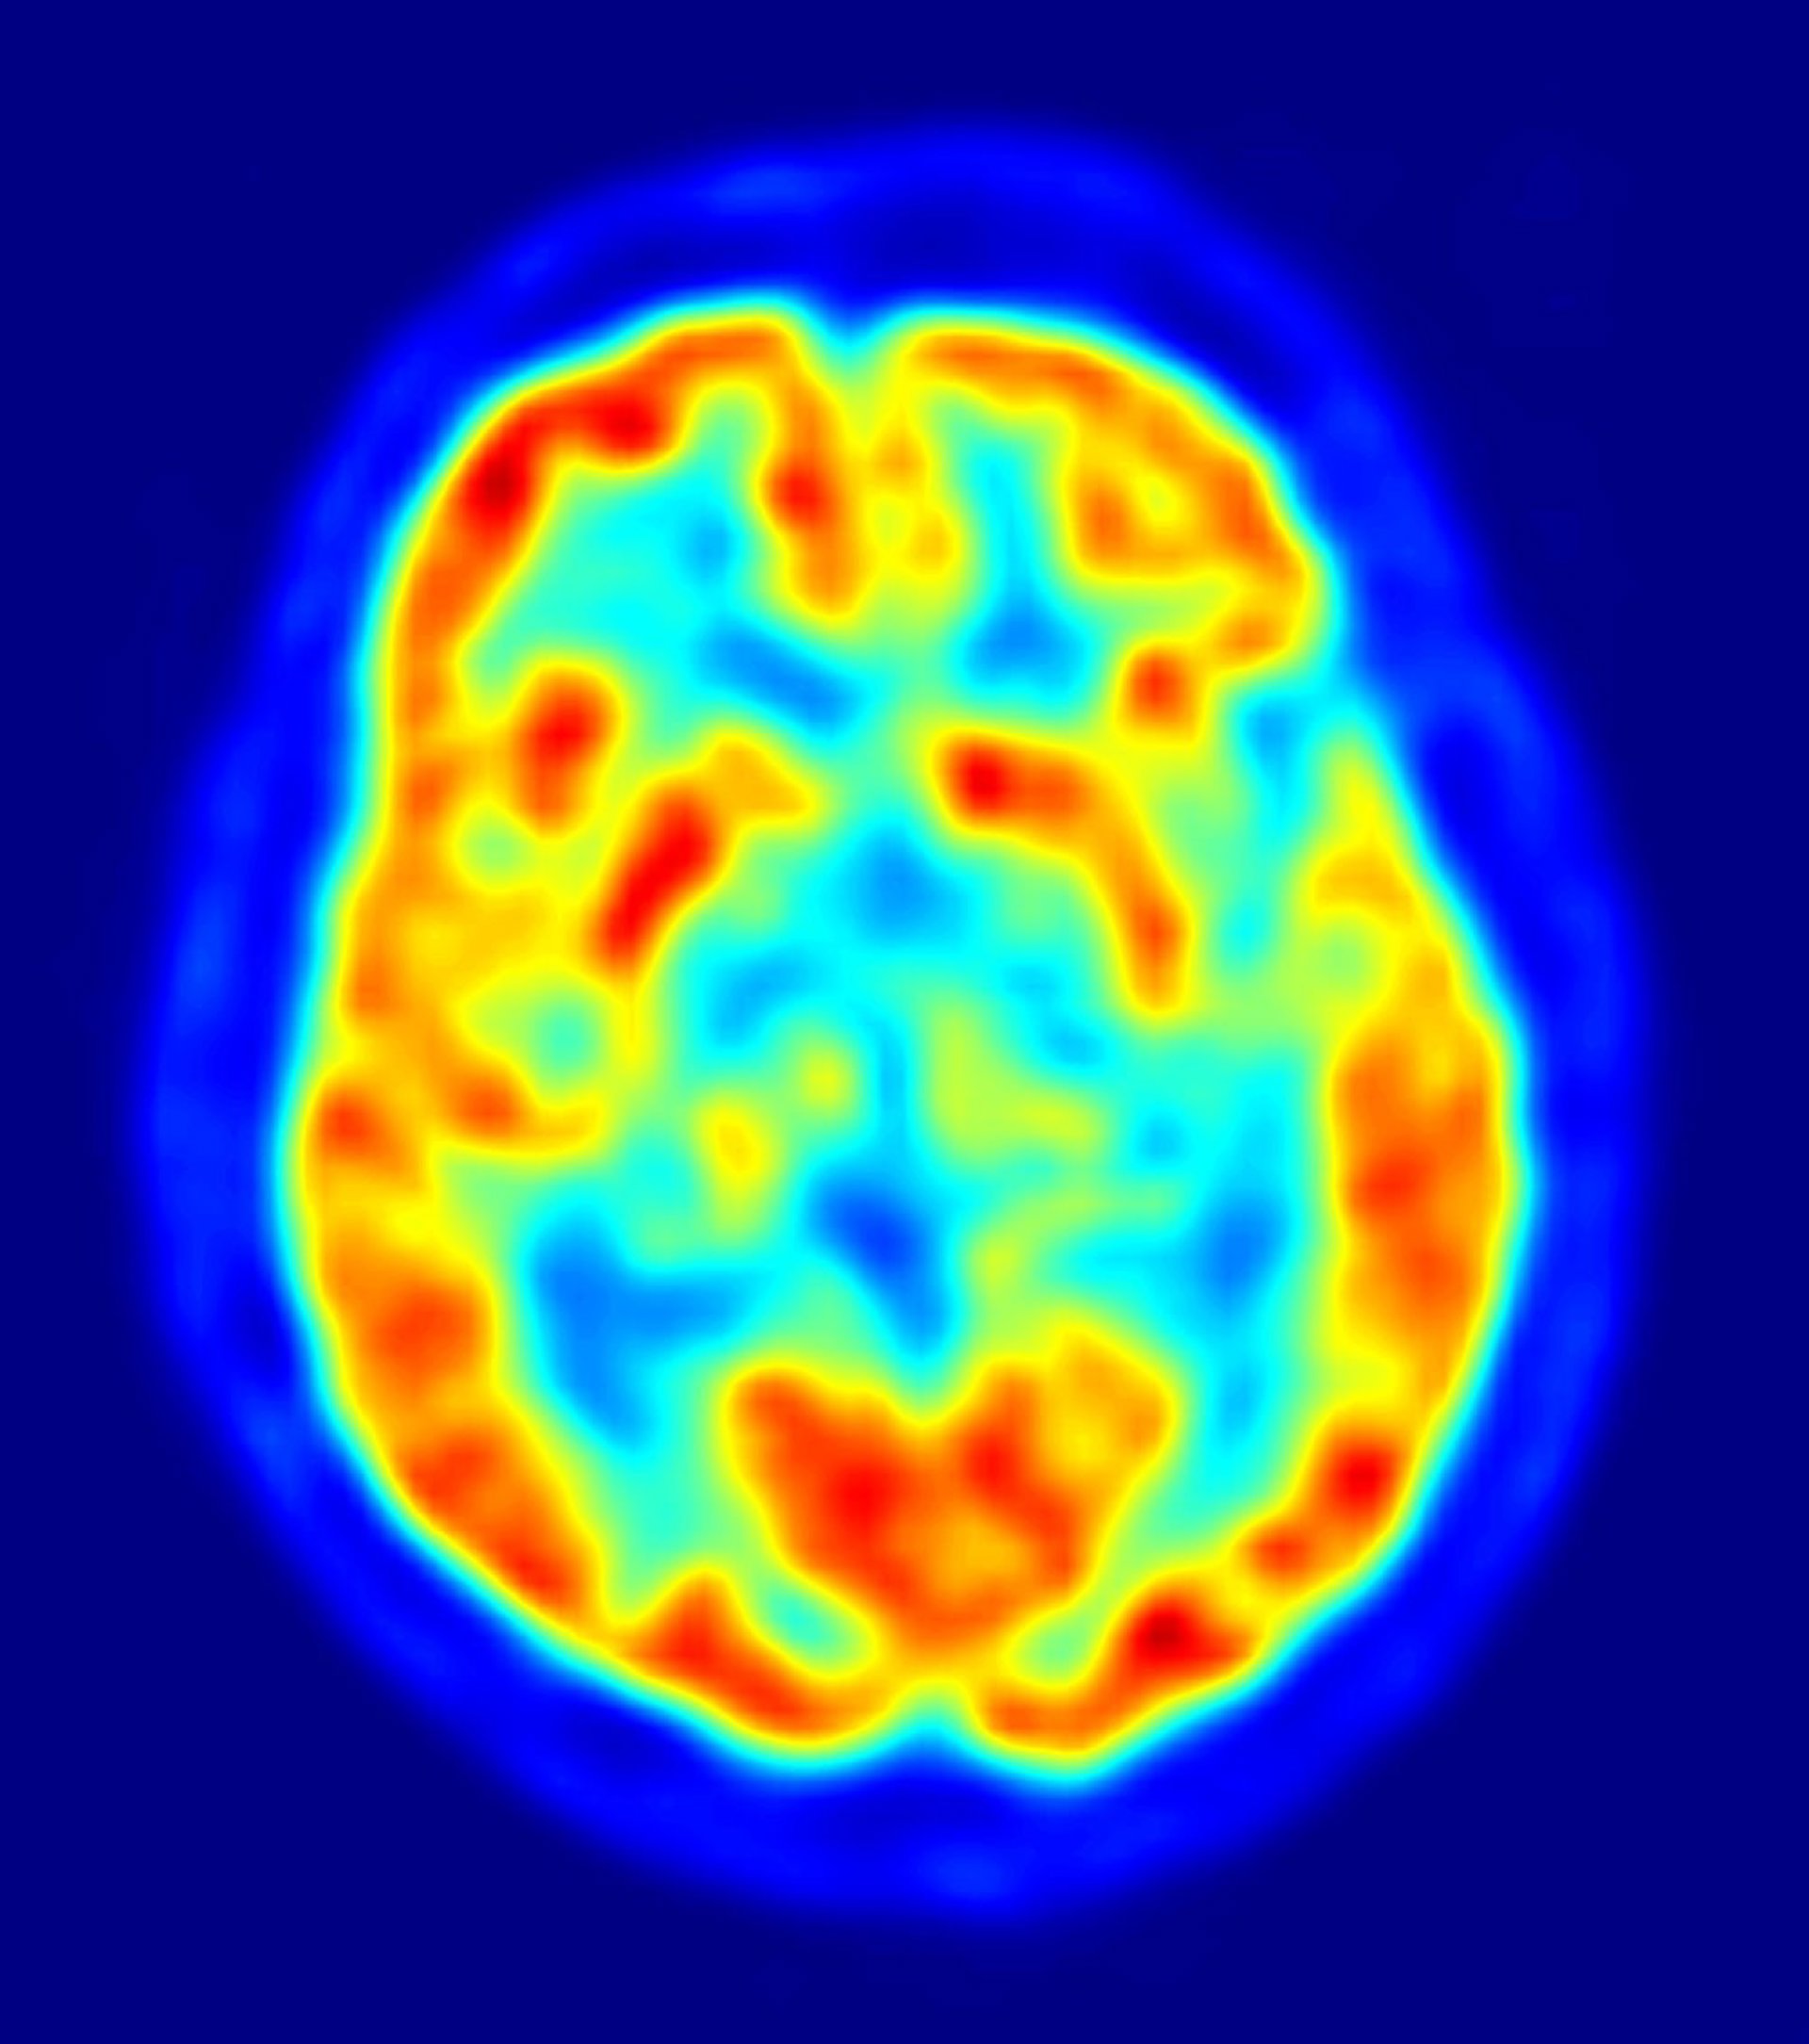

cerebro, recurso, neuronas